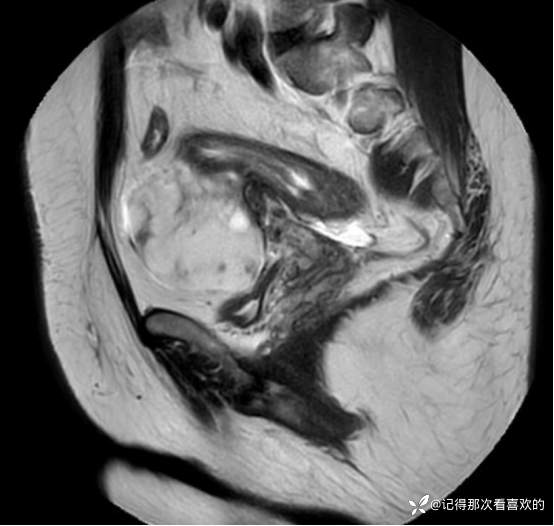

入院后查十二通道常规心电图:1、窦性心律2、逆钟向转位。余相关检验未见明显异常。于2025.05.30在静脉麻醉下行“宫腔镜诊断性刮宫术”,术顺,术后病理(2508387):(宫内容物)子宫内膜息肉。查心脏彩超(Z250530002):三尖瓣轻度反流。双侧下肢深静脉血管彩色多普勒超声(Z250530003):双侧下肢股总静脉反流,考虑双侧下肢深静脉瓣功能不全。经阴道彩超检查(Z250530004):双侧附件区低回声不均团块,考虑MT,建议进一步检查。子宫多发肌瘤。子宫内膜区低回声结节,考虑粘膜下肌瘤可能。宫颈腺体多发囊肿。盆腔MRI增强(MR109286):1.双侧附件区团块状占位,考虑MT,请结合临床。2.子宫肌层内、浆膜下多发肌瘤。3.子宫腔内异常结节灶,粘膜下肌瘤可能。4.盆腔少量积液。5.右侧髂骨内结节灶,性质待定,建议进一步检查。胸部CT(CT384707):1.双肺多发微小结节,建议随诊复查。2.气管憩室。3.扫及右肾结石?新上腹部CT平扫(CT384838):盆腔右侧占位性病变,请结合临床及MRI检查。HPV+TCT:HPV阴性;非典型鳞状上皮细胞(不能明确意义)。2025.06.03行胃肠镜,电子胃十二指肠镜检查(PG25003031):胃体溃疡(待病理);慢性萎缩性胃炎。电子结肠镜检查(PC25002608):结肠多发息肉(内镜下息肉切除+钳除)。快速石蜡病理(2508504):胃体:低分化腺癌,伴少量印戒细胞癌成分,免疫组化结果待补充报告。快速石蜡病理(2508505):降结肠:增生性息肉。